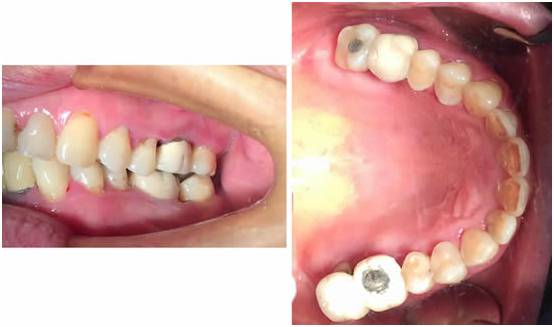

图三:术中拔出的问题牙,牙根有很严重的炎症

牙周炎导致上牙左右67四颗松动III度,右上67左上6烤瓷冠修复,右下67缺失,活动牙修复,……由于自身原因,患者要求先种植左上67.